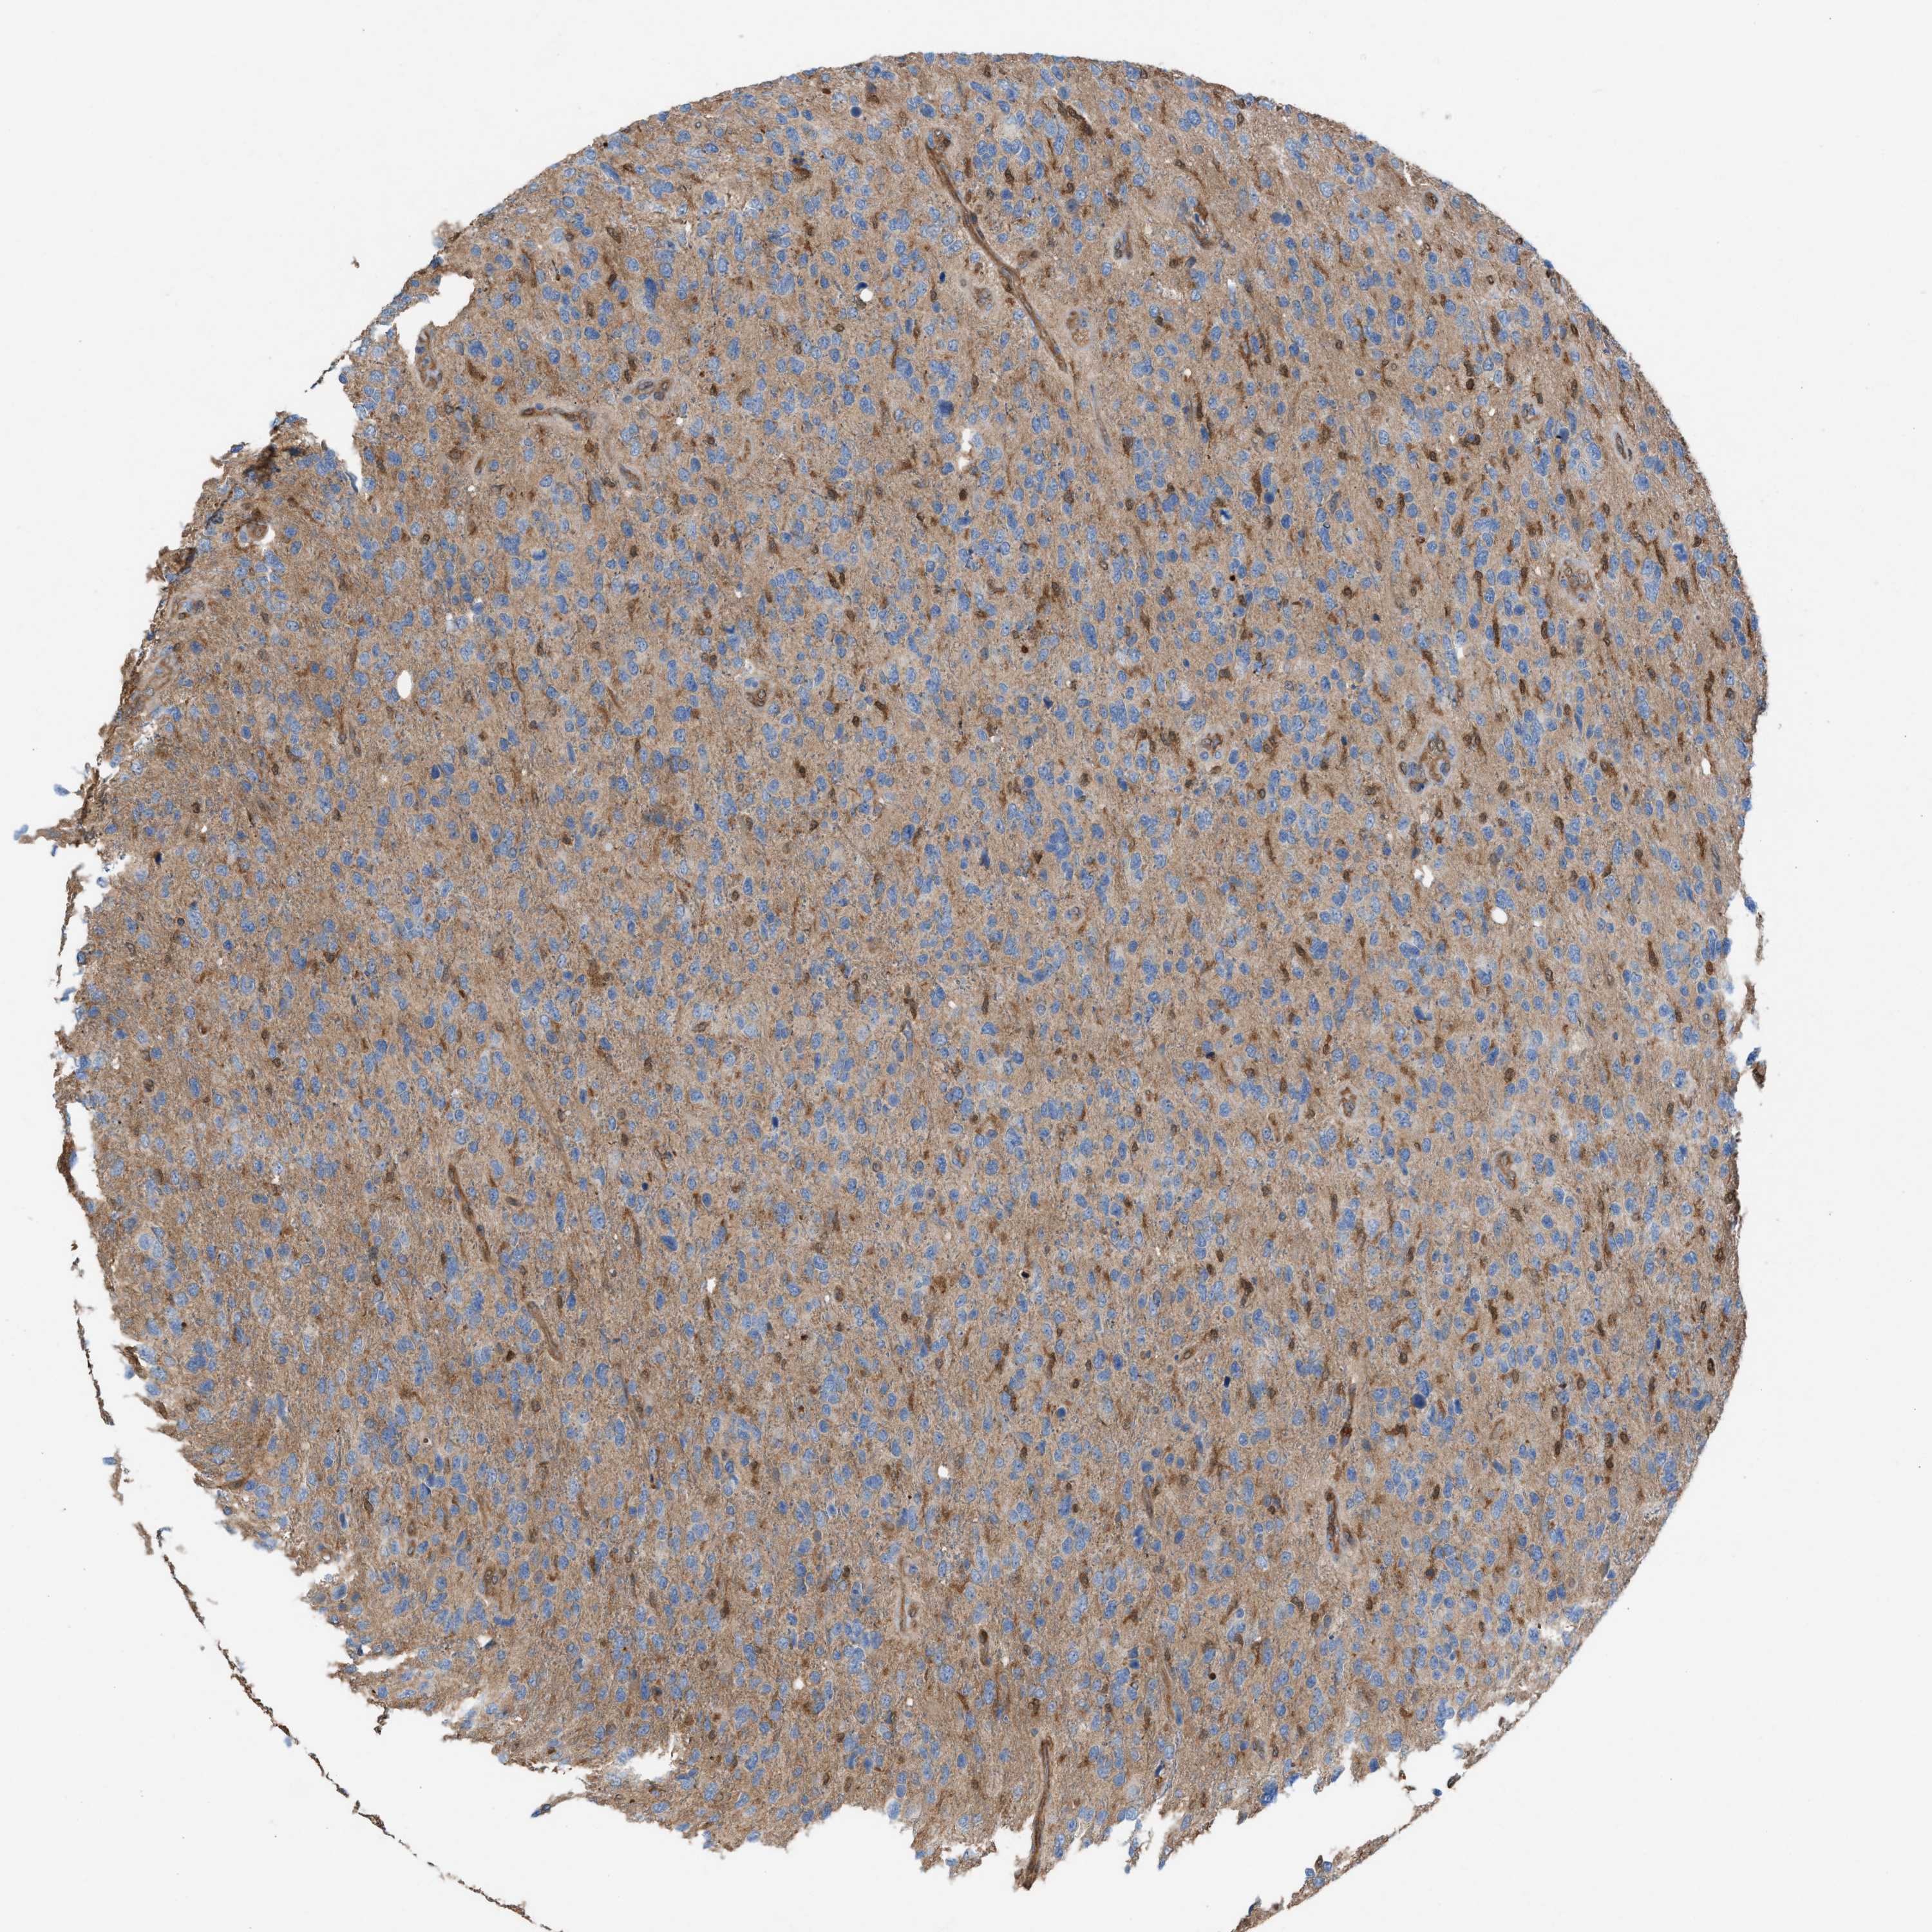

GLIOMA - Protein expressioni

A mouse-over function shows sample information and annotation data. Click on an image to view it in a full screen mode. Samples can be filtered based on level of antibody staining by selecting one or several of the following categories: high, medium, low and not detected. The assay and annotation is described here.

Note that samples used for immunohistochemistry by the Human Protein Atlas do not correspond to samples in the TCGA dataset.

Antibody stainingi

Antibody staining in the annotated cell types in the current human tissue is reported as not detected, low, medium, or high, based on conventional immunohistochemistry profiling in selected tissues. This score is based on the combination of the staining intensity and fraction of stained cells.

Each image is clickable and will lead to virtual microscopy that enables deeper exploration of all samples and also displays staining intensity scores, fraction scores and subcellular localization as well as patient and tissue information for each sample.

Antibody HPA021545

Antibody HPA021849

Staining

High

Medium

Low

Not detected

Intensity

Strong

Moderate

Weak

Negative

Quantity

>75%

75%-25%

<25%

None

Location

Nuclear

Cytoplasmic/membranous

Cytoplasmic/membranous,nuclear

Glioma, malignant, High grade

Glioma, malignant, Low grade